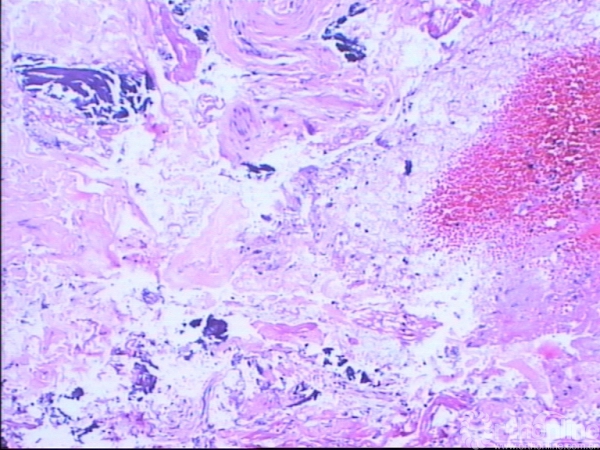

图13-7 病例二术后大体病理镜下表现

于我院行穿刺活检,病理结果为:大片出血、坏死的胶原、脂肪及死骨,另见少量囊壁样纤维组织,炎性渗出及萎缩的横纹肌,未见恶性成分,诊断为骨囊肿。

术后病理示骨囊肿。